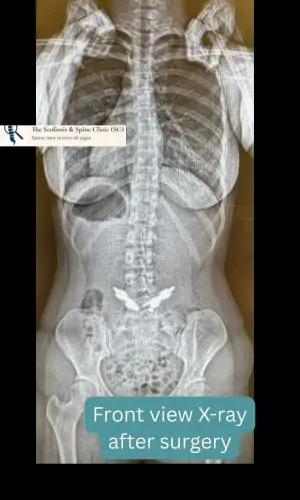

She recovered well postoperatively, regaining strength and mobility without complication. At her two-year follow-up, she reported being completely ache-free, with no residual discomfort. More importantly, she had rejoined her dancing troupe and returned to full performance—graceful, confident, and pain-free.

Post-operative PA view demonstrating restored vertebral alignment and hardware placement.